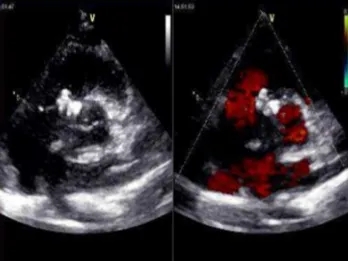

门诊心脏彩超提示:

超声多切面示:室间隔膜周部可见连续中断,局部不规则向右室膨出,呈“囊袋状”,断端回声增强,测缺口大小:左室面6.5mm、右室面2.5mm,隔瓣下残缘5mm,彩色血流示:室水平左向右分流,Vmax 473cm/s,Pgmax 89 mmHg。

各房室腔大小及大血管内径未见异常。各瓣膜厚度、弹性、开放幅度正常,彩色血流示:三尖瓣反流(少量),长度1.51cm、面积1.4cm2,容积1.0ml,Vmax 216cm/s,PGmax 16mmHg。据三尖瓣反流法估测肺动脉收缩压为28 mmHg;左室收缩功能正常,EF为74%。

术前超声与DSA复测

VSD(膜周部):室间隔膜部瘤,左室面6.5mm,右室面呈“瘤样”结构,瘤体深度7mm,出口2mm。